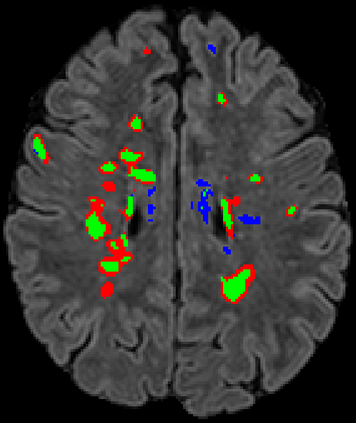

Recently, segmentation methods based on Convolutional Neural Networks (CNNs) showed promising performance in automatic Multiple Sclerosis (MS) lesions segmentation. These techniques have even outperformed human experts in controlled evaluation conditions such as Longitudinal MS Lesion Segmentation Challenge (ISBI Challenge). However state-of-the-art approaches trained to perform well on highly-controlled datasets fail to generalize on clinical data from unseen datasets. Instead of proposing another improvement of the segmentation accuracy, we propose a novel method robust to domain shift and performing well on unseen datasets, called DeepLesionBrain (DLB). This generalization property results from three main contributions. First, DLB is based on a large group of compact 3D CNNs. This spatially distributed strategy ensures a robust prediction despite the risk of generalization failure of some individual networks. Second, DLB includes a new image quality data augmentation to reduce dependency to training data specificity (e.g., acquisition protocol). Finally, to learn a more generalizable representation of MS lesions, we propose a hierarchical specialization learning (HSL). HSL is performed by pre-training a generic network over the whole brain, before using its weights as initialization to locally specialized networks. By this end, DLB learns both generic features extracted at global image level and specific features extracted at local image level. DLB generalization was validated in cross-dataset experiments on MSSEG'16, ISBI challenge, and in-house datasets. During experiments, DLB showed higher segmentation accuracy, better segmentation consistency and greater generalization performance compared to state-of-the-art methods. Therefore, DLB offers a robust framework well-suited for clinical practice.